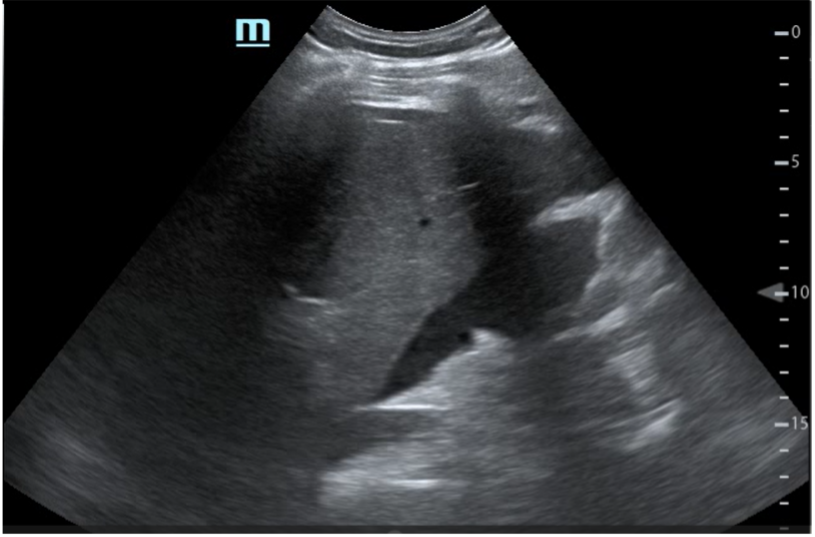

EF: Mal estado general, palidez mucocutánea, sudoración profusa. Intolerancia al decúbito supino con postura antiálgica. Abdomen: doloroso a la palpación difusa con defensa abdominal generalizada. Se realiza ecografía clínica a pie de cama objetivando líquido libre abdominal.

Paciente con cuadro de abdomen agudo ante hallazgos en ecografía clínica y anemización se solicita TAC abdominal para completar estudio. Ante diagnóstico de hematoma subcapsular esplénico y hemoperitoneo sin sangrado activo, ingresa para control del dolor y seguimiento clínico sin necesidad de intervención quirúrgica. Se solicitan serologías resultando negativas.

Tras 9 días de ingreso, el paciente fue dado de alta con seguimiento ambulatorio, mostrando mejoría clínica y reducción progresiva del hematoma en las imágenes de control.

En este caso se pone de manifiesto la gran utilidad de la ecografía clínica a pie de cama para el enfoque diagnóstico y manejo de un paciente en urgencias.